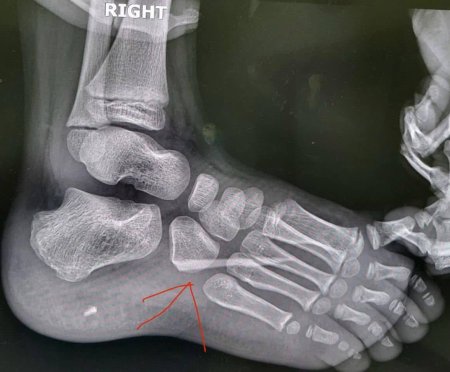

На Закарпатті лікарі успішно прооперували 7-річну дитину з аутизмом, у стопі якої виявили великий уламок скла.

Як розповіли батьки, дитина почала накульгувати, але не скаржилася на біль. Після звернення до медиків у травматолого-ортопедичному відділенні лікарні провели клінічний огляд та рентген, під час якого і виявили стороннє тіло.

Хірургічне втручання пройшло успішно — уламок скла видалили без ускладнень, стан дитини задовільний.